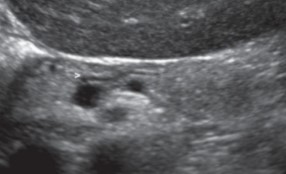

How does acute pancreatitis appear on US?

Enlarged

Hypoechoic